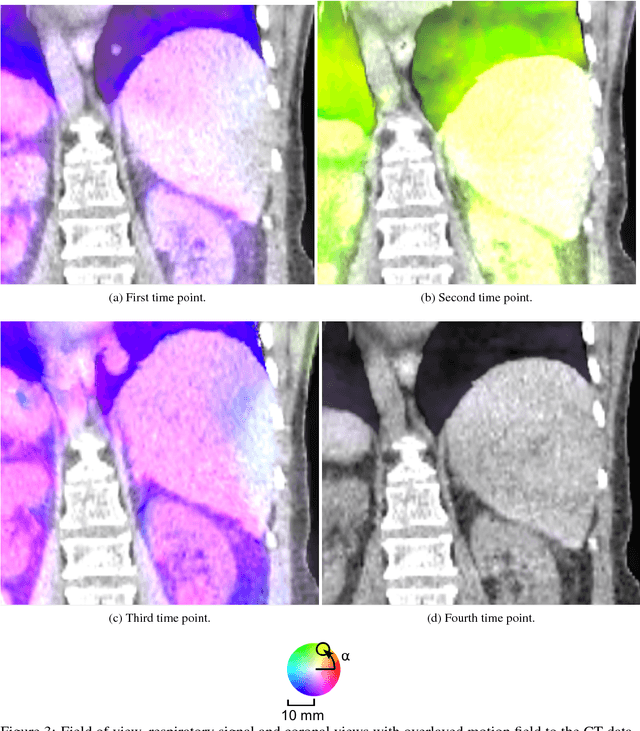

Abstract:Virtual reality (VR) training simulators of liver needle insertion in the hepatic area of breathing virtual patients currently need 4D data acquisitions as a prerequisite. Here, first a population-based breathing virtual patient 4D atlas can be built and second the requirement of a dose-relevant or expensive acquisition of a 4D data set for a new static 3D patient can be mitigated by warping the mean atlas motion. The breakthrough contribution of this work is the construction and reuse of population-based learned 4D motion models.

Abstract:Current virtual reality (VR) training simulators of liver punctures often rely on static 3D patient data and use an unrealistic (sinusoidal) periodic animation of the respiratory movement. Existing methods for the animation of breathing motion support simple mathematical or patient-specific, estimated breathing models. However with personalized breathing models for each new patient, a heavily dose relevant or expensive 4D data acquisition is mandatory for keyframe-based motion modeling. Given the reference 4D data, first a model building stage using linear regression motion field modeling takes place. Then the methodology shown here allows the transfer of existing reference respiratory motion models of a 4D reference patient to a new static 3D patient. This goal is achieved by using non-linear inter-patient registration to warp one personalized 4D motion field model to new 3D patient data. This cost- and dose-saving new method is shown here visually in a qualitative proof-of-concept study.